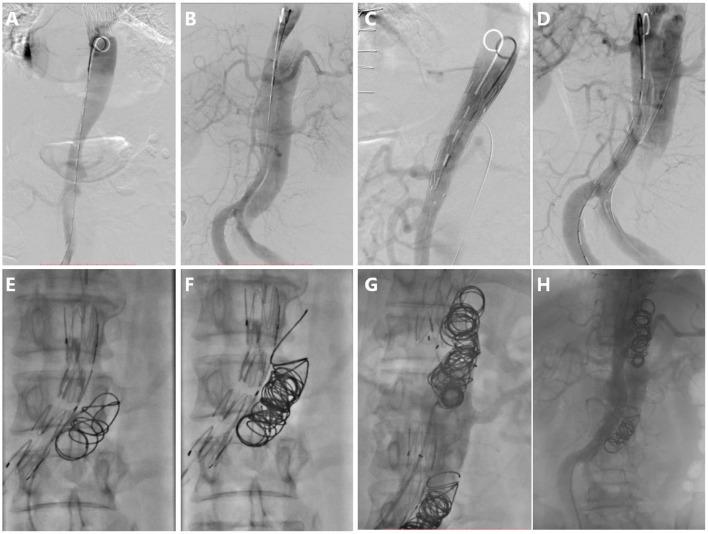

This prospective single-center clinical study included patients suffering from symptomatic distal dilatation of CADAV after aortic repair treated with RBS from January 2015 to December 2019 and followed up regularly for at least 2 years. Stent grafts were implanted first to cover distal tears and expand the true lumen. Device embolization was performed to induce proximal and distal segmental false lumen thrombosis (FLT) apart from the level of the ostia of vital branches. Successful RBS was performed in 13 patients. Significant differences were found in maximum true lumen diameter ( < 0.05), blood flow area in false lumen (FL) ( < 0.001), and the ratio of blood lumen to FL area ( < 0.05) between the pre-procedure and the latest follow-up results. No aortic rupture, vital branches occlusion, thoracic and abdominal pain, or death occurred during hospitalization and follow-up.